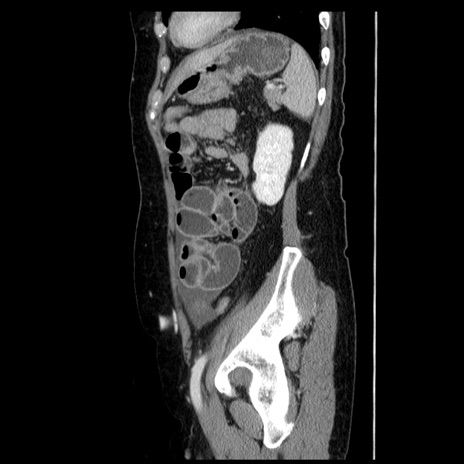

症例6(矢状断像)

【症例】50歳代女性

【主訴】下腹部痛

【現病歴】本日朝より下痢2回あり。 昼食を食べた後、嘔吐3回、下腹部痛認め、症状軽快せず、当院救急搬送。

最終食事:本日昼(生ものなし)。 昨日の夜、刺身を食ぺたとのこと。周囲に同様の症状の者なし。普段、排便は毎日あるとのこと。

【既往歴】卵巣癌術後(8年前に当院で卵巣摘出)

【身体所見】 意識清明、腹部:平坦、腸蠕動音→、やや硬、下腹部自発痛・圧痛あり、反跳痛あり、筋性防御なし。

【データ】WBC 16000、CRP 0.01